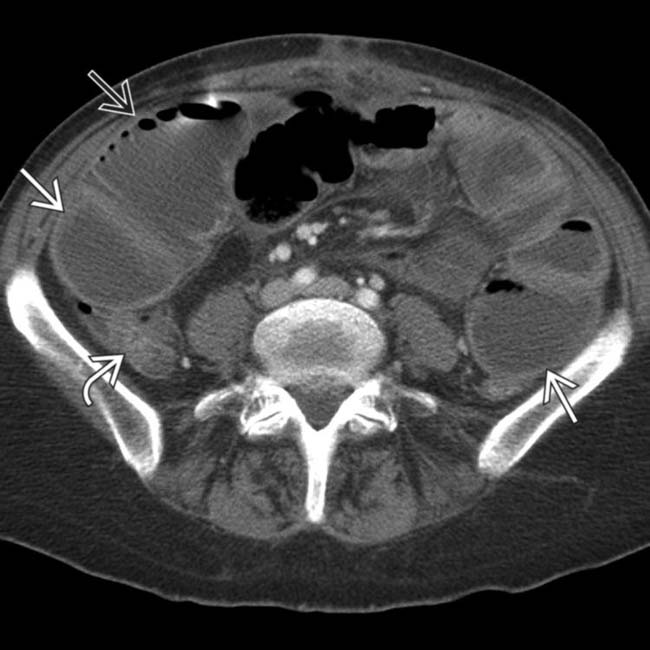

Slippage of gastric band in a 54yearold woman. Abdominal plain Gastric Band Obstruction Radiology Misplacement of the band is usually caused by the surgeon's lack of experience and rarely occurs when the surgeon is experienced [1]. A gastric band is a popular form of bariatric surgery and is a surgically placed device, used to assist in weight loss and is adjustable. The band may be placed in the perigastric fat (fig. Mild to moderate. Gastric Band Obstruction Radiology.